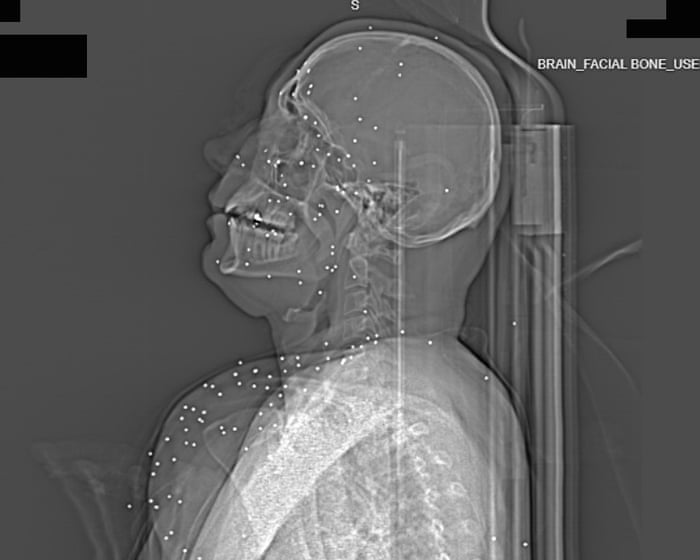

‘Deliberate targeting of vital body parts’: X-rays taken after Iran protests expose extent of catastrophic injuries

Exclusive: Expert analysis of images from one hospital suggests severe trauma to the face, chest and genitals was caused by metal birdshot and high-calibre bullets

Across the planes of Anahita’s* face, white dots shine like a constellation. Some gleam from inside the sockets of her eyes, others are scattered over the young woman’s chin, forehead, cheekbones. A few float over the dark expanse of her brain.

Each dot represents a metal sphere, about 2-5mm in size, fired from the barrel of a shotgun and revealed by the X-ray camera for a CT scan. Shot from a distance, the projectiles, known as “birdshot”, spray widely, losing some of their momentum. At close range, they can crack bone, blast through the soft tissue of the face, and easily pierce the eyeball’s delicate globe. Anahita, who is in her early 20s, has lost at least one eye, possibly both.